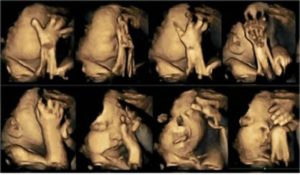

↓喫煙時の胎児のエコー画像です。

見ても、吸えますか?

「くさい、くるしい、うぁーーー」

苦しんで嫌がっているように見えます。

そんなつもりはなくても、すでに虐待だ。